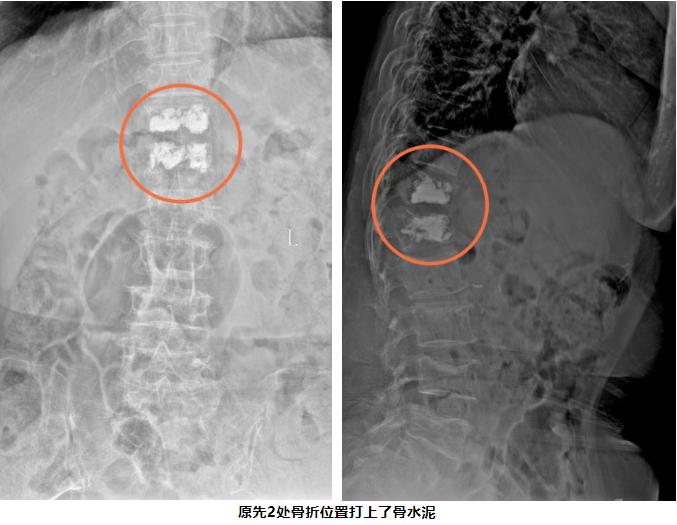

去年12月底,方奶奶意外扭伤,导致胸椎和腰椎两处骨折。当时,她患有重度骨质疏松、高血压和糖尿病等多种基础疾病,承受着骨折导致的剧烈疼痛,让家人和医生都揪紧了心。医院骨科团队经过精准评估,为她实施了“经皮胸腰椎椎体成形术”,手术结束,方奶奶的疼痛感就明显减轻了。第二天,她就能在搀扶下下床活动,配合系统的抗骨质疏松治疗,恢复得非常顺利。

经皮椎体成形术(PVP)

经皮椎体成形术是在影像引导下,将穿刺针经皮穿刺到病变椎体后,向椎体内注入骨水泥,以达到增强椎体强度和稳定性、防止塌陷、缓解腰背疼痛,甚至部分恢复椎体高度的一种微创脊柱外科技术。